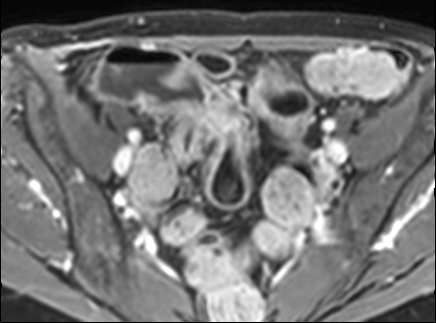

Hồi tràng cuối đang viêm cấp tính với dày thành nhiều và tín hiệu thành ruột vừa (phù nề thành ruột) trên hình ảnh T2 axial có fat-sat.